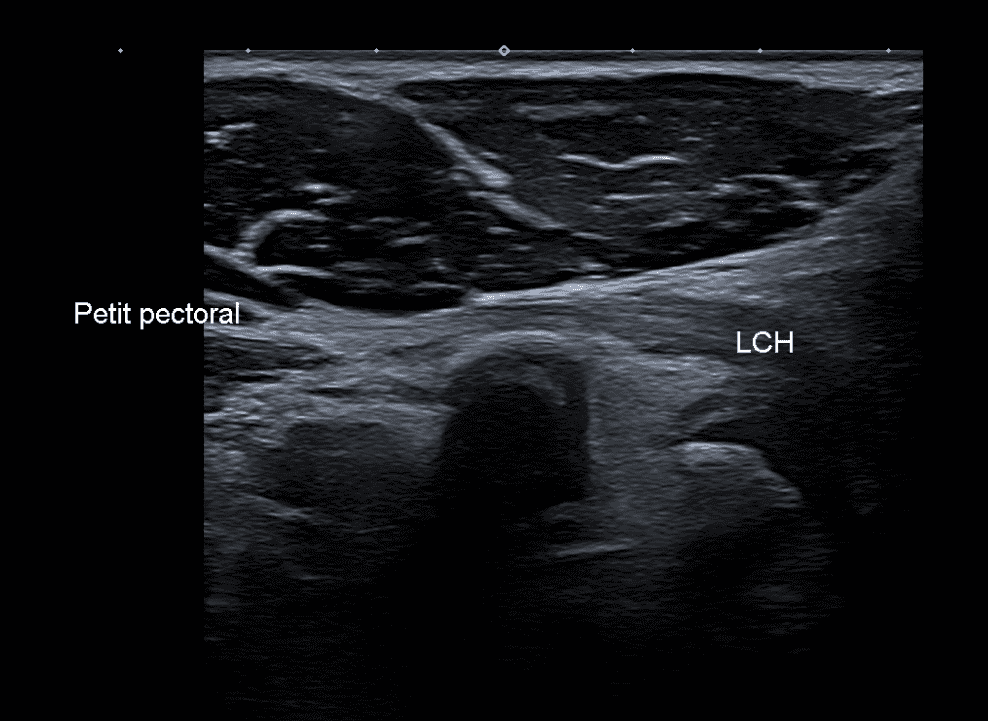

Continuité du petit pectoral avec le ligament coraco-huméral

Variante anatomique du tendon du muscle petit pectoral.

US